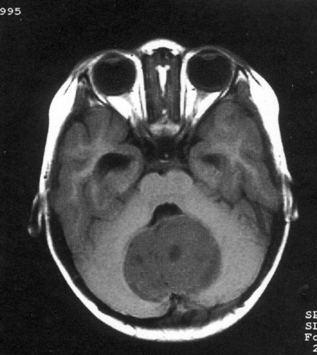

问题 病历摘要:??患儿男性,11岁。半年前开始出现行走不稳,常无故跌倒。半月前出现发作性剧烈头痛,伴恶心呕吐。体检:T36℃,P100次/分,R22次/分,BP100/60mmHg,神清,言语较缓慢,双眼外展约不及边,双眼侧视时有小幅度水平眼震。四肢肌力正常,右上肢肌张力较低,坐位姿势不稳,常不自主摇晃,双上肢指鼻不准,行走蹒跚步态,足距扩大,身前倾。 下一步应首先采取哪些措施?提示:多次缝合伤口,仍有脑脊液渗漏。